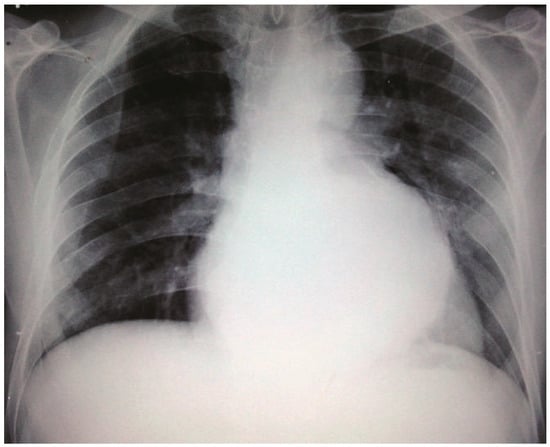

Case report. A 63-year-old hypertensive male presented with atypical chest discomfort and breathlessness on exertion [...]